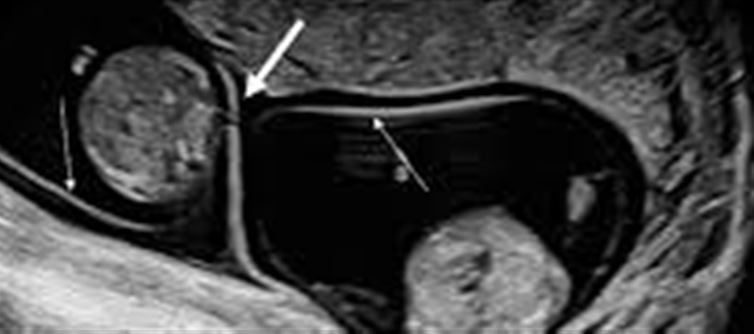

They're typically diagnosed at some point of the first-trimester ultrasound, which indicates one placenta and a skinny membrane separating the two sacs.